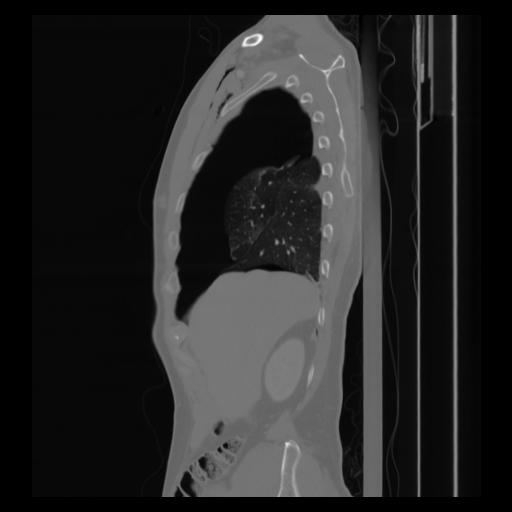

30 CUERPO,CE,Sagittal,3.000,CUERPO,Sagittal,